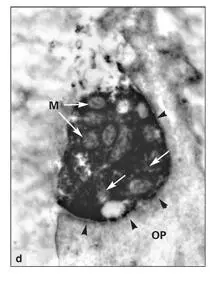

Because the cell processes of fibroblasts and odontoblasts can be confused with unmyelinated nerve fibers, special staining techniques are needed to accurately distinguish nerve fibers and their terminals. Protein gene product 9.5, a neuron-specific protein, has been used to identify pulpal nerve fibers at both the light and electron microscopic level (see Figs 2-10ato 2-10d). 140 , 144Fibers containing protein gene product were present in both radicular and coronal predentin. Nerve endings in the predentin have also been identified by immunocytochemistry for calbindin, a calcium-binding protein found in high concentrations in nerve cells. 145Tracer experiments with tritiated proline injected into the brainstem nuclei of the trigeminal nerve have provided convincing proof of a rich supply of sensory nerve terminals in the predentin and dentinal tubules. 146

Figs 2-10a to 2-10dNerve structure of a human premolar. (Human protein gene product [PGP] 9.5 antibody stain. Adapted from Maeda et al 140with permission from Elsevier Science.)

Fig 2-10dElectron immunocytochemistry. The nerve terminals contain mitochondria (M) and many smooth vesicles (arrows) . Although the plasma membranes of the nerve terminals are in close apposition to the plasma membrane of the odontoblastic process (OP) (arrowheads) , no evidence of a synaptic structure is present. (Original magnification × 12,000.)